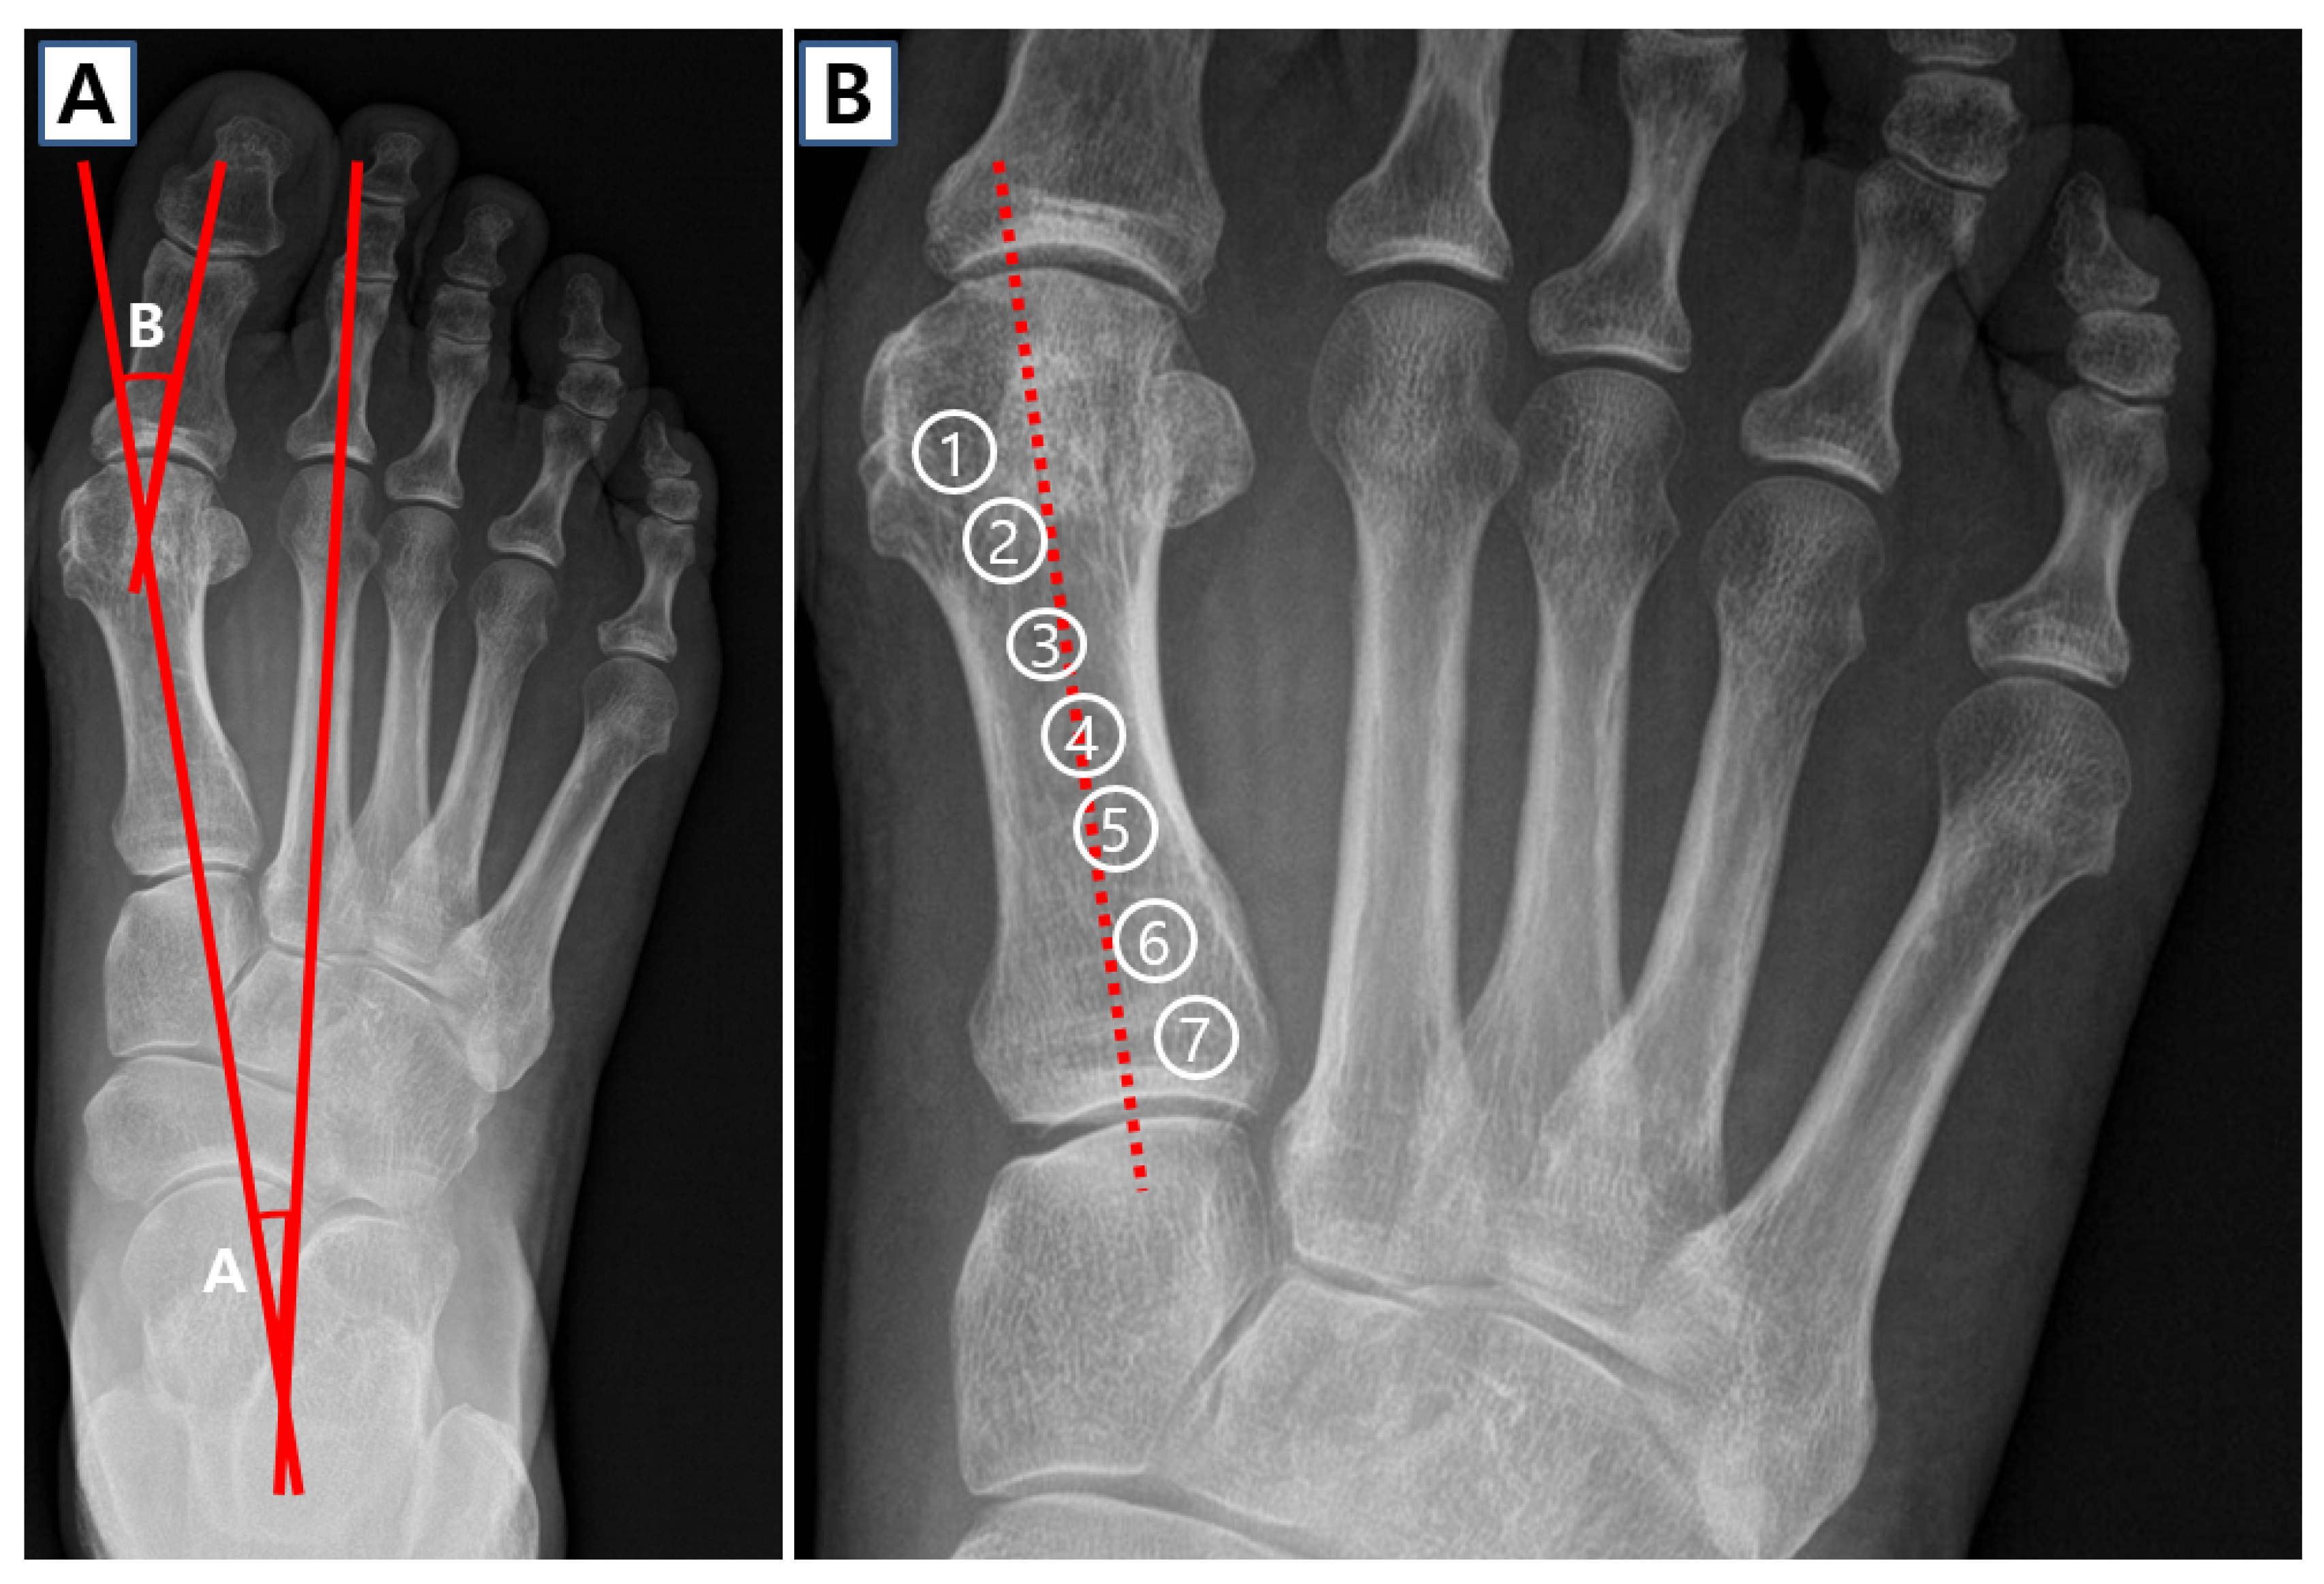

Dr. George Williams is not only a board-certified podiatrist serving the Palm Harbor community—he's a recognized innovator who has contributed to advancing the field of foot and ankle surgery. His pioneering work spans wound healing techniques, surgical evaluation tools, and precision-guided procedures that improve patient outcomes across Florida and beyond.

Explore Dr. Williams' innovative techniques that have advanced wound care through clinical research, surgical precision, and evidence-based treatment protocols.